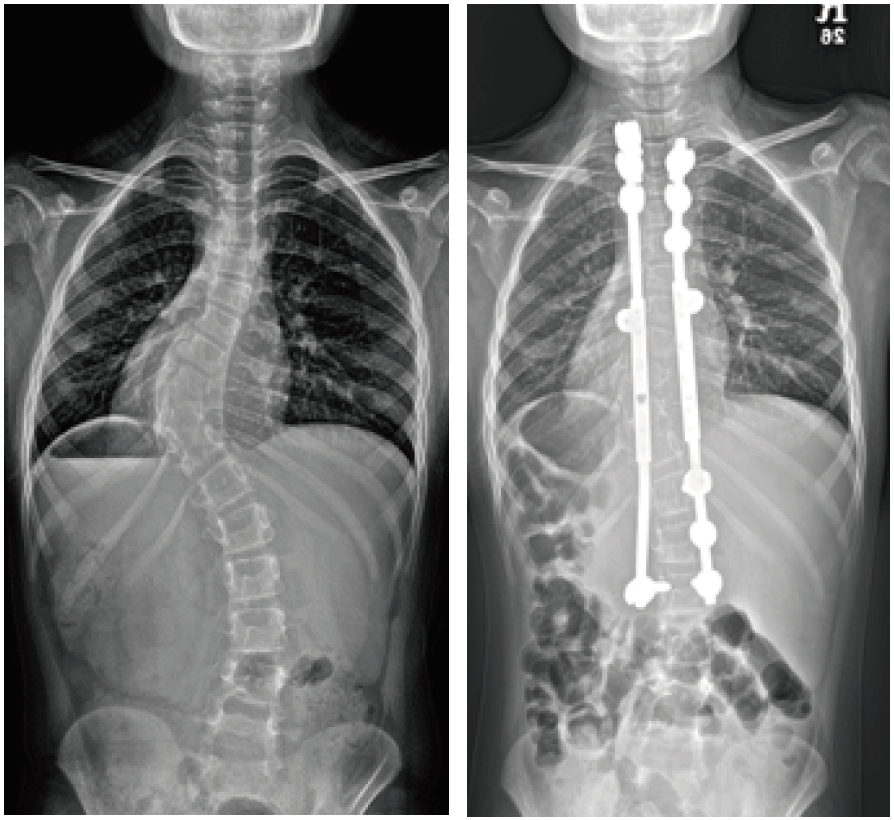

- 성장이 많이 남은 어린 아동에서 측만증이 심할 경우 그림과 같이 만곡의 위아래에만 일시적 고정 후 성장할 때 마다 강봉을 늘려 성장이 종료될 때까지 만곡의 진행을 방지합니다.

- 성장이 많이 남은 경우에는 특발성에서와 같이 성장형 강봉을 이용하여 척추체의 상하부를 고정하고 성장에 따라 강봉을 늘려갑니다.

- 휠체어 보행만 하는 경우 골반의 비대칭도 고려하여야 합니다. 앉은 자세에서 골반이 평행하고 이에 따라 어깨도 평행하게 해주는 것이 좋습니다. 마비가 있는 환자의 경우 수술 범위가 일반적으로 매우 길게 됩니다.